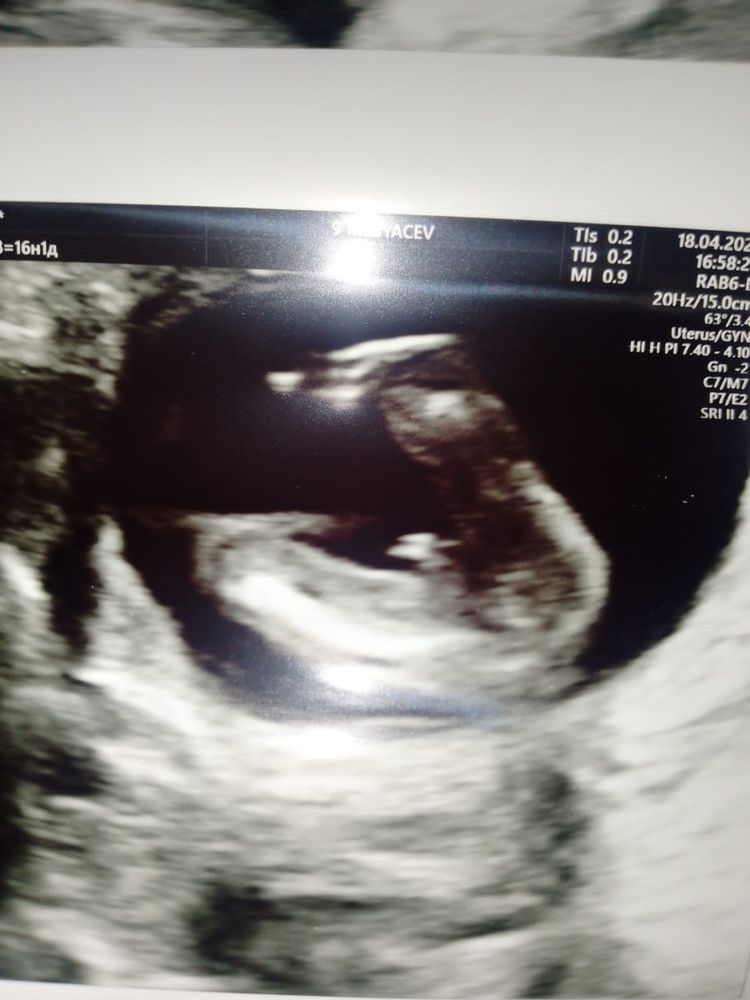

ИзображениеУ меня такое фото с 1 скрининга (13,4 нед.). Врач с уверенность сказала что мальчик. Но моя надежда на девочку не покидает меня 😄 чем то-фото похоже на ваше. Сдала кровь, 5 июня узнаю пол.

У меня точно такая же фотка,сказали мальчик Изображение на втором скрининге подтвердили